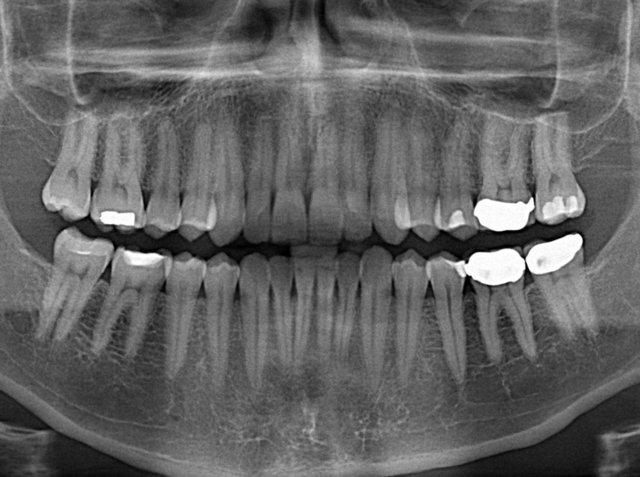

وی با انتقاد از بیتوجهی به محافظت بیماران و همراه بیماران با وسایل پوششی مناسب برای سایر اعضای بدن که قرار نیست اشعه به آن تابیده شود، گفت: گاهی آنقدر به این موضوع بیتوجهی میشود که مردم نیز نسبت به آن آگاه نیستند. به عنوان مثال هنگامی که میخواهیم عکس رادیولوژی از دندان داشته باشیم باید غده تیروئید در گردن با پوشش مناسب سربی پوشیده شود تا جلوی تابش اشعه به آن گرفته شود که معمولا این اتفاق نمیافتد و مورد غفلت واقع میشود و این درحالی است که غده تیروئید غده مهم و حساسی در بدن انسانها است. اهمیت این امر از نظر بهداشتی و حفاظتی تا حدی است که اگر دندانپزشکی این غفلت را انجام دهد جریمه این کار در حد تعطیلی مرکز است.

گورانی به منظور بیان این موضوع که در کشور ما استفاده بیرویه از پرتو در امور پزشکی زیاد است بیان کرد: مثلا در برخی از اورژانسهای بیمارستانهای عمومی از هر بیماری که وارد اوژانس میشود یک عکس رادیولوژی میگیرند آنهم در شرایطی که ممکن است اصلا لازم نبوده باشد و این هم در دسته پرتوگیریهای غیرضروری قرار میگیرد. یا اینکه متاسفانه بعضی از بیمهها برای پرداخت هزینههای دندانپزشکی فرد را مجبور میکنند حتما بعد از اتمام ترمیم دندان یک عکس رادیولوژی اضافی بگیرد که پیوست پرونده کنند. بدیهی است این اقدام غیر علمی با توجه به تعداد زیاد آسیبهای دندان و نیاز گسترده به ترمیم دندان در کشور، سالیانه علاوه بر تحمل هزینههای گزاف به مردم، موجبات پرتوگیری قابل توجهی در افراد را فراهم میآورد.